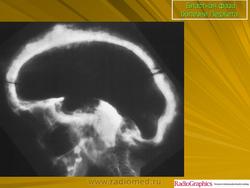

Смешанная фаза.

Бластная фаза

Принято различать три фазы развития П. б.: очаговая интенсивная резорбция кости (остеолитическая, или деструктивная, фаза), смешанная фаза, когда наряду с рассасыванием кости идут процессы новообразования ее, и остеобластическая, или склеротическая, фаза с образованием типичных мозаичных структур.